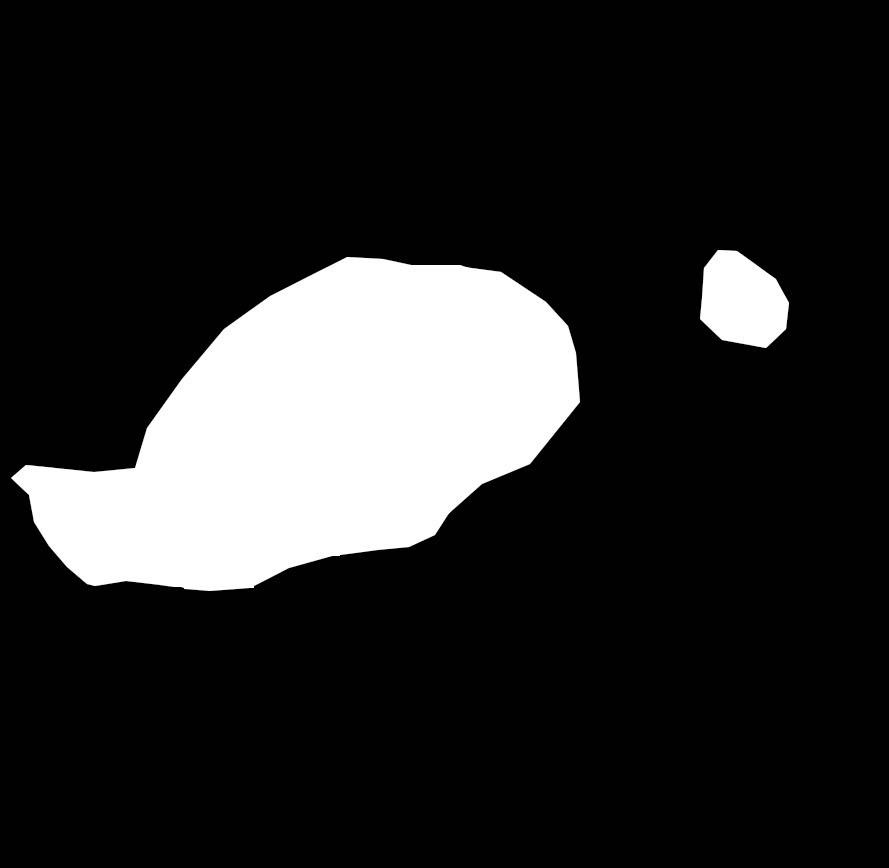

In order for the LDI scans to be comparable with BAM binary segmentations, a number of processing steps were conducted. LDI scans can have different sizes, scales, and cropping in comparison to their corresponding burn images. As BAM uses the burn 2D colour images as the input for creating the binary burn segmentations, the LDI scans were first aligned with their corresponding burn images and converted into the same size as those images. Once the LDI scans are aligned with input images and their colors are processed in order to create binary masks, quantitative comparisons with BAM segmentations were conducted. For this purpose, we utilised the manual segmentations of burn areas from burn images validated by clinicians.

Moreover, as discussed later, it was discovered that the LDI scan color palette, which demonstrates different healing potentials, would classify uninjured areas and background noise in the image as burns with poor blood flow. In a clinical setting, this misclassification does not lead to a serious issue as scans are reviewed by clinicians who can easily differentiate between normal skin/background and burn area. However, since the processing of LDI scans is conducted by computer vision, this issue needed to be resolved. This was addressed by removing the non-burn areas from the LDI scans before processing LDI scans by multiplying the aligned LDI scans with the manual segmentations of burn areas resulting in LDI scans that show various healing potentials (or various degrees of burn) in the burn area only.

Once the heatmaps with the highest correlation coefficients are selected, these high-resolution visualizations are utilized as the input to make binary segmentation masks as illustrated in Figure 4(i). The generation of masks uses Gaussian components of the maps to find thresholds (Figure 4(ii)) and subsequently uses the highest Intersection-Over-Union (IOU) values (Figure 4(iii)) between the binary masks generated and the Grad-CAM to select the final mask. The generated binary segmentation mask lastly undergoes a post-processing step in order to filter out the noise/false positive regions and produce the final BAM mask (Figure 4(iv)), which can be used for super-positioning on the input image (Figure 2b).